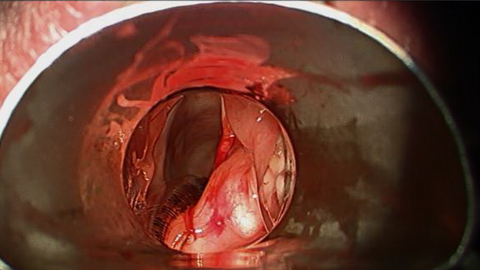

Intraoperative Images